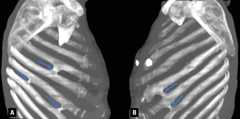

The fused rib prevalence was 0.45%. Nine fused ribs were found in 5 (2.26%) cases, and the mean age was 51. Five fusions were found in 1 of the cases (Fig. 3). Fused rib was observed in 4 males and 1 female. While 4 of the 9 fused ribs were on the right side, 5 were on the left. There was no difference between the sexes regarding fused rib variation (p > 0.05). Fusions were found between the 5th and 6th, 6th and 7th, and 7th and 8th ribs (Table 4).

Figure 3.Right side(A) and left side(B) thoracic computer tomography images of 5 fusion centres in the same case.